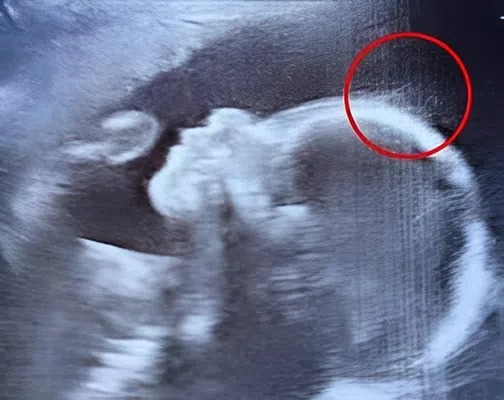

But within minutes of the scan beginning, something unusual caught everyone’s attention.

The technician paused, leaning closer to the monitor, adjusting the angle slightly. Emily noticed the expression on her face shift from professional focus to one of curious surprise.

“Just a moment,” the technician said softly, fingers moving deftly over the controls. She zoomed in on the image. The room fell quiet. Then, with a light laugh, almost of disbelief, she asked, “Is that… hair?”

Emily blinked. “Hair?” she repeated, unsure she had heard correctly. At five months, it seemed improbable that the baby could have noticeable hair.

The technician smiled, her eyebrows raised. “It certainly looks like it.”